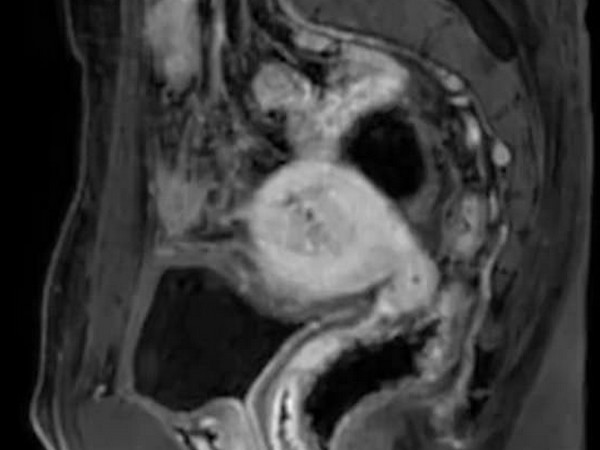

వైద్యులు అతడికి స్కానింగ్ తీయగా, షాకింగ్ విషయం బయటపడింది. అతడికి గర్భాశయం, అండాశయాలతో సహా స్త్రీ పునరుత్పత్తి అవయవాలు ఉన్నాయని తేలింది. దీంతో స్త్రీ పునరుత్పత్తి అవయవాలను తొలగించుకోవాలని నిర్ణయించుకున్నాడు. కాగా, గత నెలలో అతడికి స్పెషలిస్ట్ హాస్పిటల్‌లో మూడు గంటలపాటు శస్త్రచికిత్స విజయవంతంగా జరిగింది.